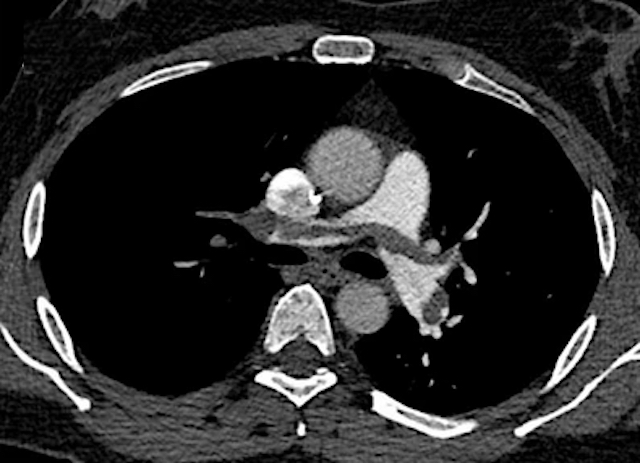

L’angioscanner pulmonaire est l’examen de référence pour la détection de l’embolie pulmonaire (EP) mais il est associé à une exposition importante aux rayonnements et à l’utilisation de produits de contraste iodés, ce qui comporte des risques inhérents pour le patient.

Les résultats de la méta-analyse ont d'identifier 148 références, parmi lesquelles 35 études ont été incluses pour l'extraction des données. Onze de ces études fournissaient des données complètes sur la dose de rayonnement, le volume de produit de contraste et la qualité d'image. Elles ont systématiquement démontré que les protocoles utilisant une faible tension du tube (≤ 80 kVp) et un volume de produit de contraste réduit (≤ 60 ml), en particulier lorsqu'ils étaient associés à des techniques de reconstruction itérative, permettaient de réduire significativement le CTDIvol et la dose efficace de 50% à plus de 80%, tout en préservant la qualité diagnostique des images.